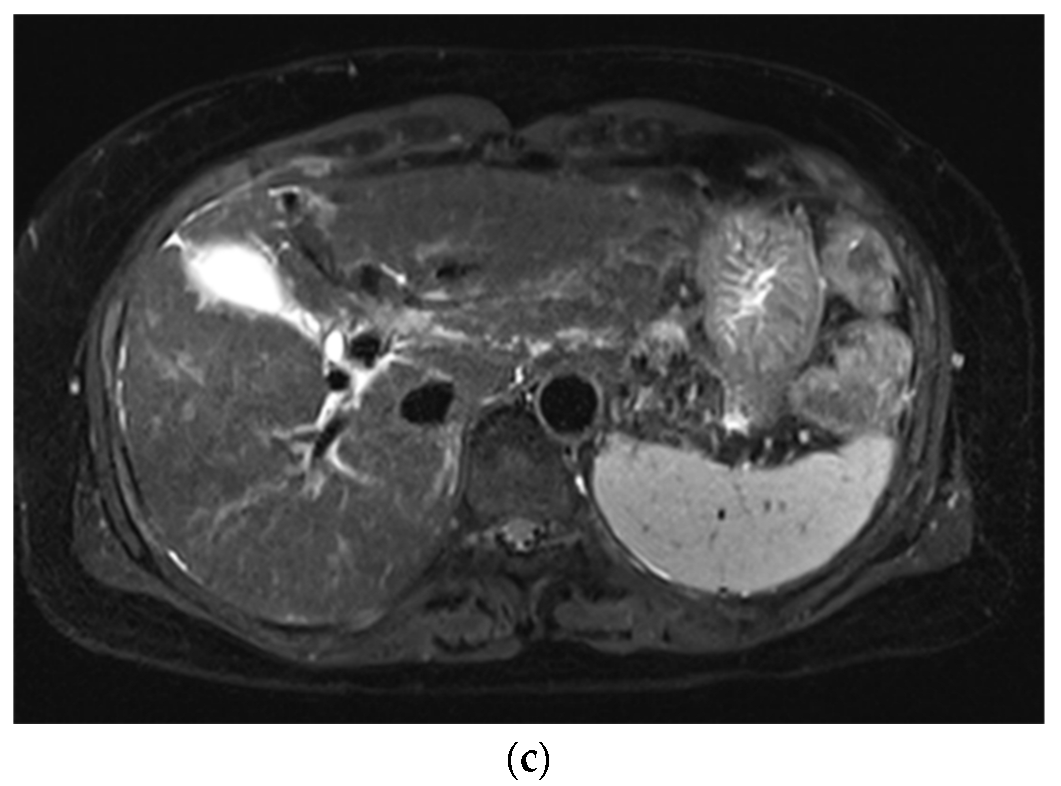

3.1. Subjective Image Quality

3.2. Lesion Assessment